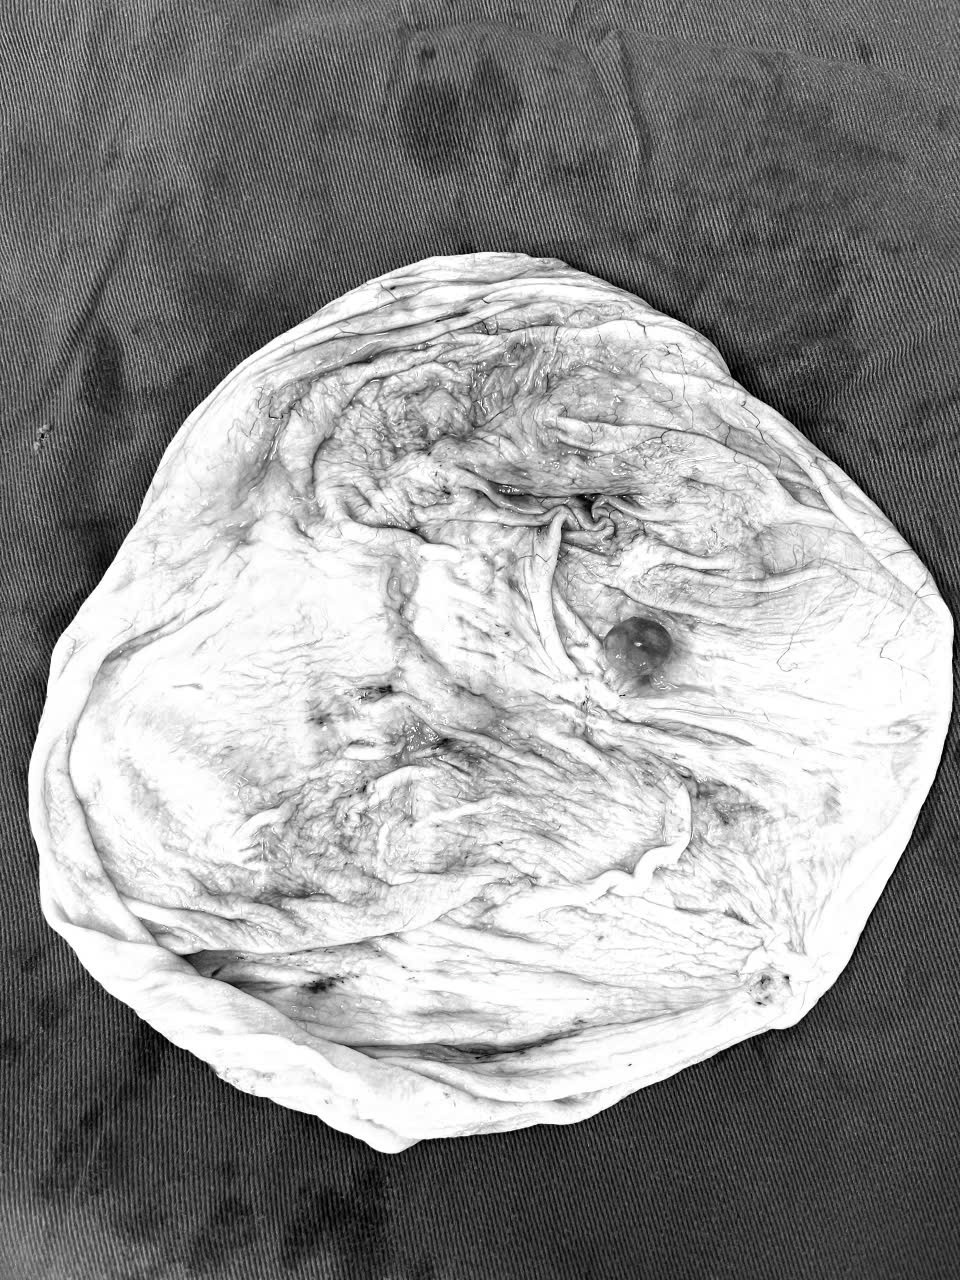

Các bác sĩ khoa Ngoại tổng hợp đã phối hợp với bác sỹ Gây mê hồi sức thực hiện ca phẫu thuật nội soi cắt u phúc mạc cho bệnh nhân. Khi vào ổ bụng thấy khối u lớn chèn ép các quai ruột, Phúc mạc thành dính khối u. Các bác sĩ đã khéo léo bóc tách loại bỏ trọn vẹn khối u căng bóng chứa dịch bên trong, chọc hút hết dịch trong khối u. Sau gần 2giờ, Êkíp phẫu thuật đã loại bỏ khối u phúc mạc kích thước 20x 30 cm. Hiện nay bệnh nhân đã ổn định, rút sonde dẫn lưu ổ bụng và ăn uống bình thường.

Êkíp phẫu thuật đã loại bỏ khối u phúc mạc kích thước 20x 30 cm cho BN

Khối u sau phẫu thuật